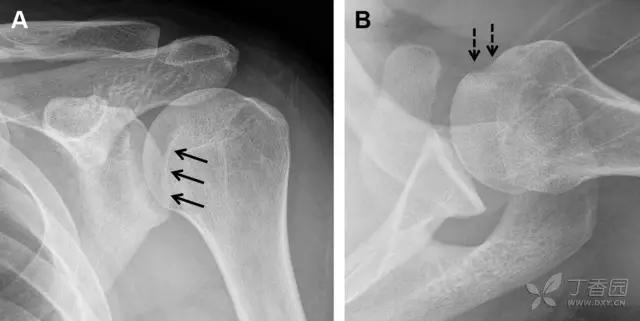

图 7 肩关节后脱位伴有反 Hill–Sachs 损伤。(A)外旋位前后位片可见一硬化带(黑箭头),此「凹槽征」与肱骨头关节面平行;(B)腋位片进一步证实了骨折的存在